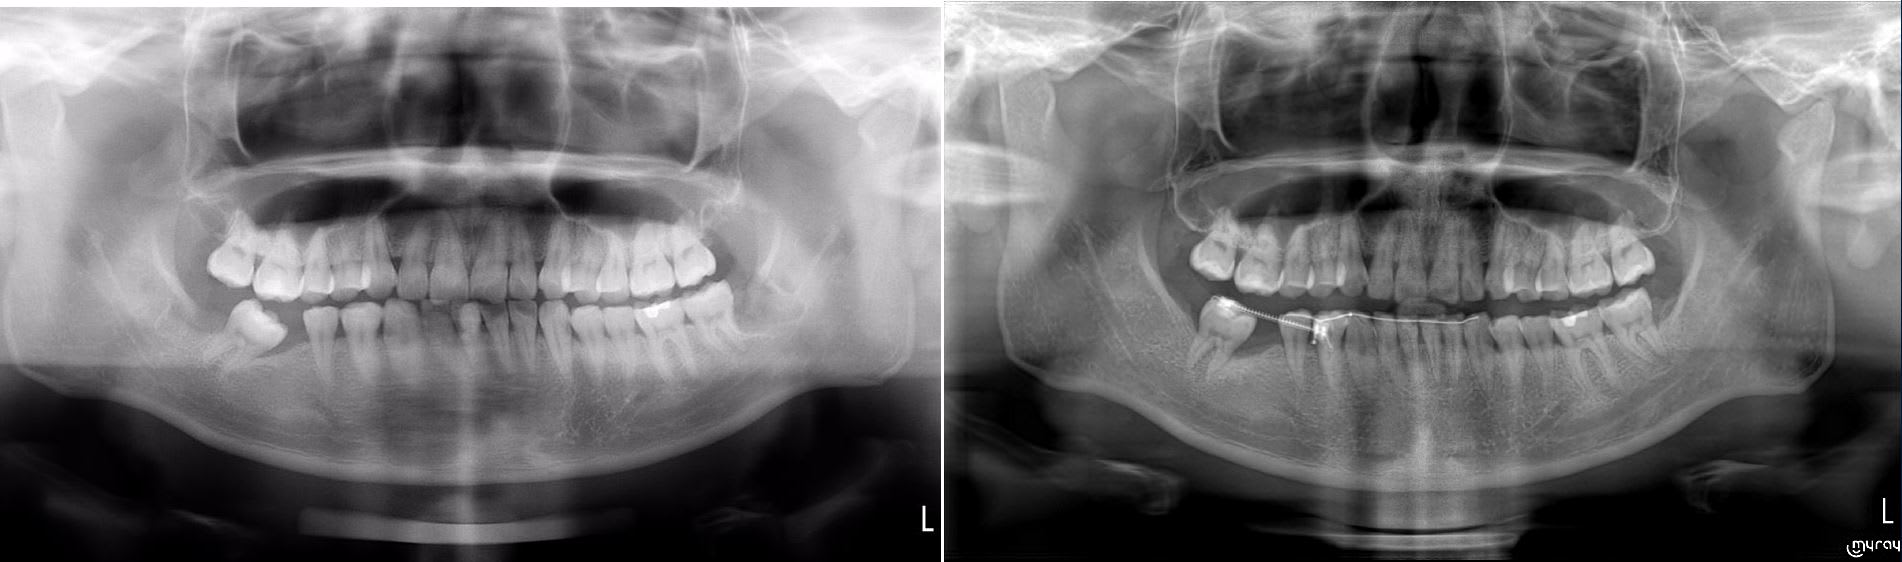

Aujourd'huit c'était la journée. Patient pas venue depuis deux mois , appareillage en place depuis un peut mois de trois mois, compter encore un ou deux mois et il y auras assez d'espace pour poser les implants.

Un dentiste qui voulait ingresser une 47 pour faire une couronne sur implant sur 17, je lui ai fais le labo pour son premier cas. IL avait pensé ingresser avec des gouttières ( patient pas coopérant et qui ne veut pas de truc volumineux en bouche, ou des minivisse ( pas évident évident dans ce cas de figure ) .

Et lundi un patient pour ouverture d'espace avec patient pas content. Pas content car le dentiste à essayer de faire ça avec une minivisse et ça n'a pas marché ( et oui une minivisse + chainette ça ne fait que du tipping.